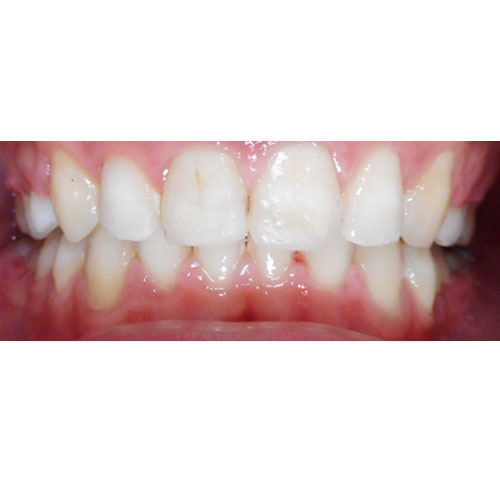

Nasze rezultaty